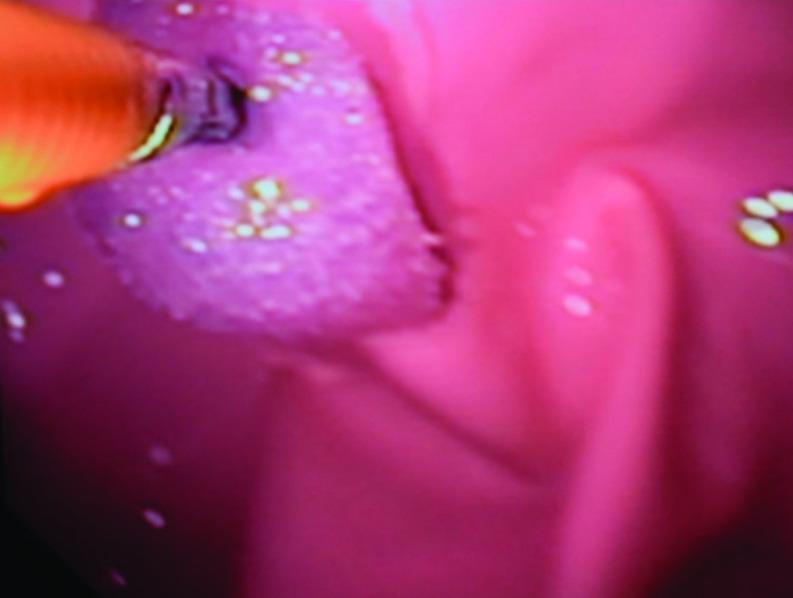

A mechanical simulator was created from inexpensive items easily acquired at a hardware store and in the hospital. Total cost of the simulator was approximately $120 USD. To validate the simulator, experienced endoscopists completed a training session with the device. A seven-question Likert scale survey (1 - strongly disagree to 5 - strongly agree) was completed after the session evaluated the simulated experience versus live upper endoscopies and the device's ability to meet the goals of the FES curriculum.

Eight proficient endoscopists completed the training session and survey and agreed that the device closely replicated live colonoscopies and would meet all training requirements in the FES curriculum. Mean responses to all seven survey questions ranged from 3.8-4.4.

This device is a cost-effective method for simulating live upper endoscopies and is appropriate for use in FES training.